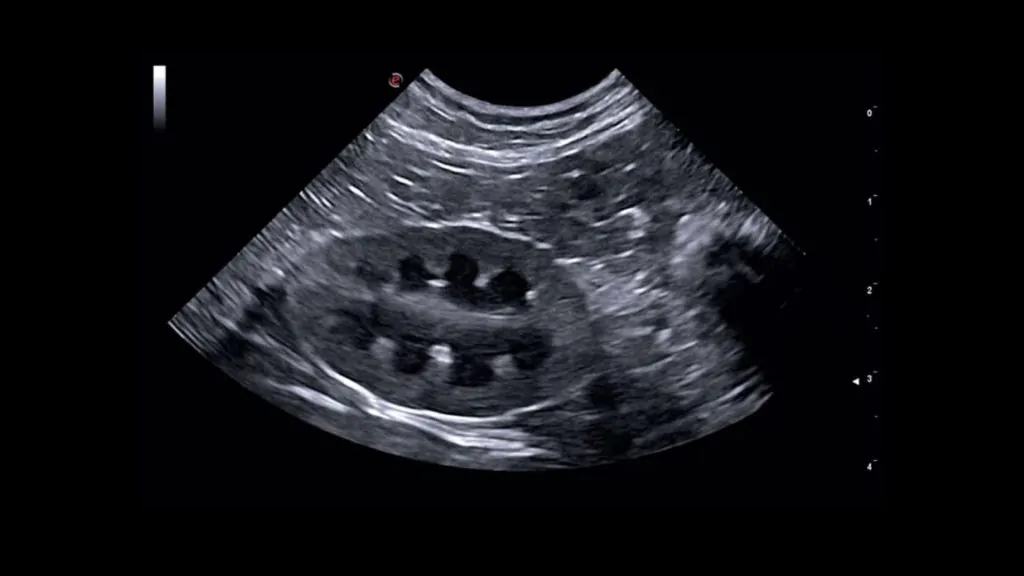

Mide ve Bağırsaklar

Yabancı cisim, invaginasyon, duvar kalınlaşması, inflamatuvar hastalıklar ve bazı tümöral süreçlerin değerlendirilmesinde kullanılabilir. İnceleme öncesi açlık genellikle önerilir.